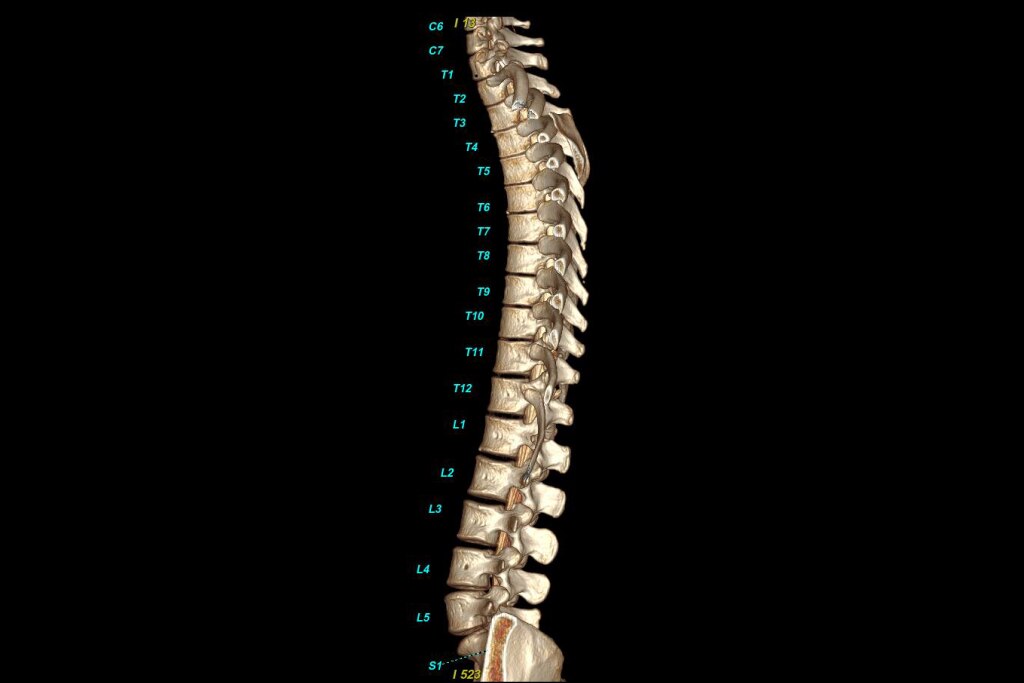

Structural heart:

Streamlined workflow for planning and augmented guidance with Valve Assist 23.

• -33% volume of contrast media4 and-33% X-ray dose in TAVI procedures5.

-78% volume of contrast media, -28% procedure time and -25% fluoroscopy time in LAAC procedures6.